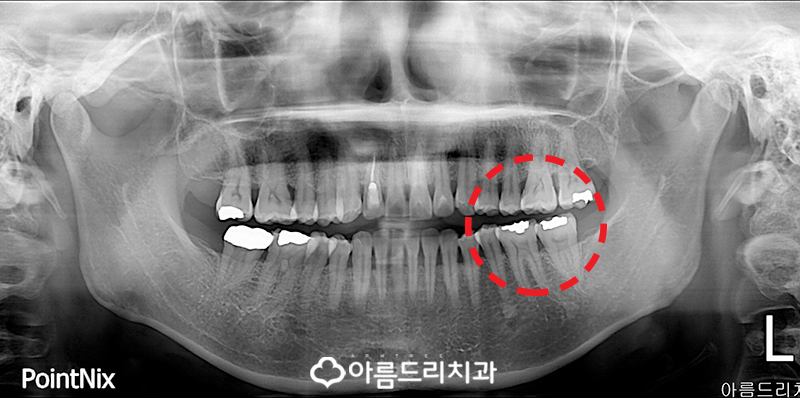

혹여나 예상했던 것과 다르게 다른 치아의 문제가 발생하는 경우도 있기 때문에 전체 적인 치아의 상태를 파악하기 위해 파노라마 X-ray 사진을 촬영하였는데, 예상했던대로 좌측의 어금니 앞치아가 문제가 있는 것 으로 보이는 것을 확인할 수 있었죠.